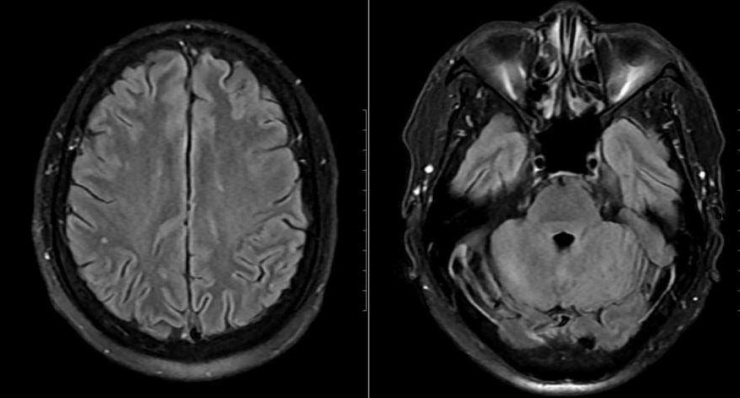

Mặc dù chưa có biểu hiện thần kinh rõ ràng, bệnh nhân vẫn được chọc dò dịch não tủy để loại trừ biến chứng. Kết quả cho thấy dịch não tủy có tăng tế bào và protein, phản ứng Pandy dương tính, xác định viêm não - màng não. Bên cạnh đó, hình ảnh MRI sọ não phát hiện ổ tổn thương nhỏ tại thùy chẩm trái.

Tổn thương phát hiện trên phim chụp MRI của bệnh nhân. Ảnh: BVCC